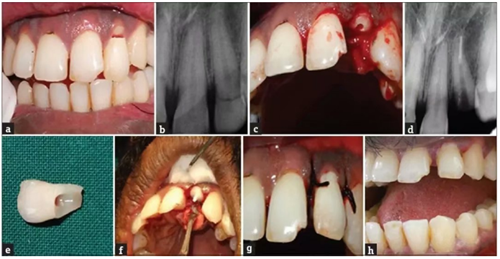

病例2

患者,男,19歲,因騎車(chē)發(fā)生事故導(dǎo)致上頜中切牙外傷??谇粰z查可見(jiàn)牙齒22牙冠冠部EllisⅢ級(jí)牙折,從牙冠的牙冠中1/3到舌側(cè)齦下2mm處。將牙齒折斷部分無(wú)創(chuàng)地取出并儲(chǔ)存在生理鹽水中,完成根管治療。如前所述,使用雙固化樹(shù)脂粘結(jié)劑通過(guò)合適的纖維樁將折斷部分的牙折片與剩余的牙齒部分重新連接。最后,復(fù)位皮瓣,縫合。

a. 術(shù)前口內(nèi)照片;b. 術(shù)前根尖片;c. 拔除牙齒折斷片;d. 根管充填;e. 牙齒折斷片;f. 折斷片再?gòu)?fù)位;g. 術(shù)后2年。